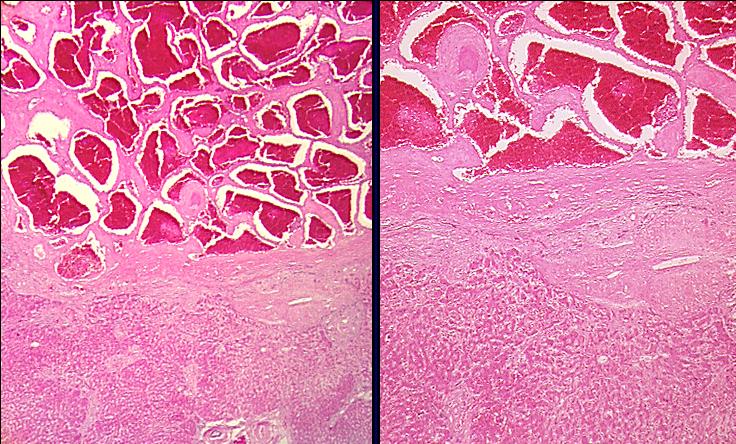

Histologie:

- gewucherte dilatierte Hohlräume

- von Endothel ausgekleidet, zum Teil auch mit

glatter Muskulatur

- prall mit Erythrozyten gefüllt

- von kräftigen bindegewebigen Septen

durchzogen

- oft Druckatrophie des umgebenden Gewebes

- Zentralvene

- Portalfeld

- normales

Lebergewebe

- zellreiches

umgebendes Bindegewebe

- blutgefüllte

weite Gefäßmißbildungen

mit Endothelauskleidung